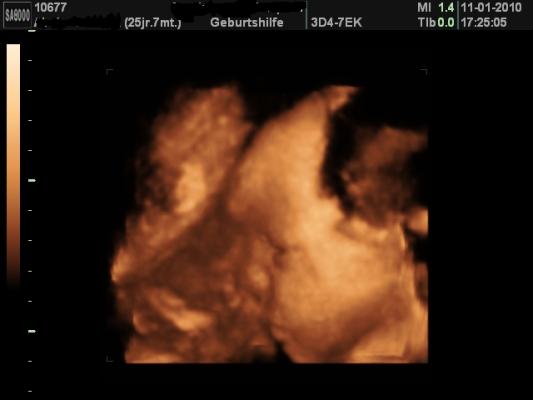

Hallo Mädels, war heut bei der VU bei SSW 30+5, alles ok... Baby ist zeitgerecht entwickelt und hat heut mal richtig mitgemacht beim 3D Shooting... beim CTG allerdings ist sie mir immer abgehauen, mussten sie die ganze Zeit suchen... ich bin soooo verliebt in unsere kleine Maus... könnte die Welt umarmen... Gewicht: +12kg... ahhhhhhhhhhhhhhhh Sie liegt in SL, mein Blutdruck 105/70 und Fundusstand: Ribo/3, Urin ok! Anbei das 3D Foto, die Kleine von der Seite, an der Nase ist die Nabelschnur, die ist immer mal wieder vorbei geschwommen... und sie hat die Augen auf, total niedlich. vlg Manu

Bild zu VU Bericht und 3D Foto - Forum für März - Mamis